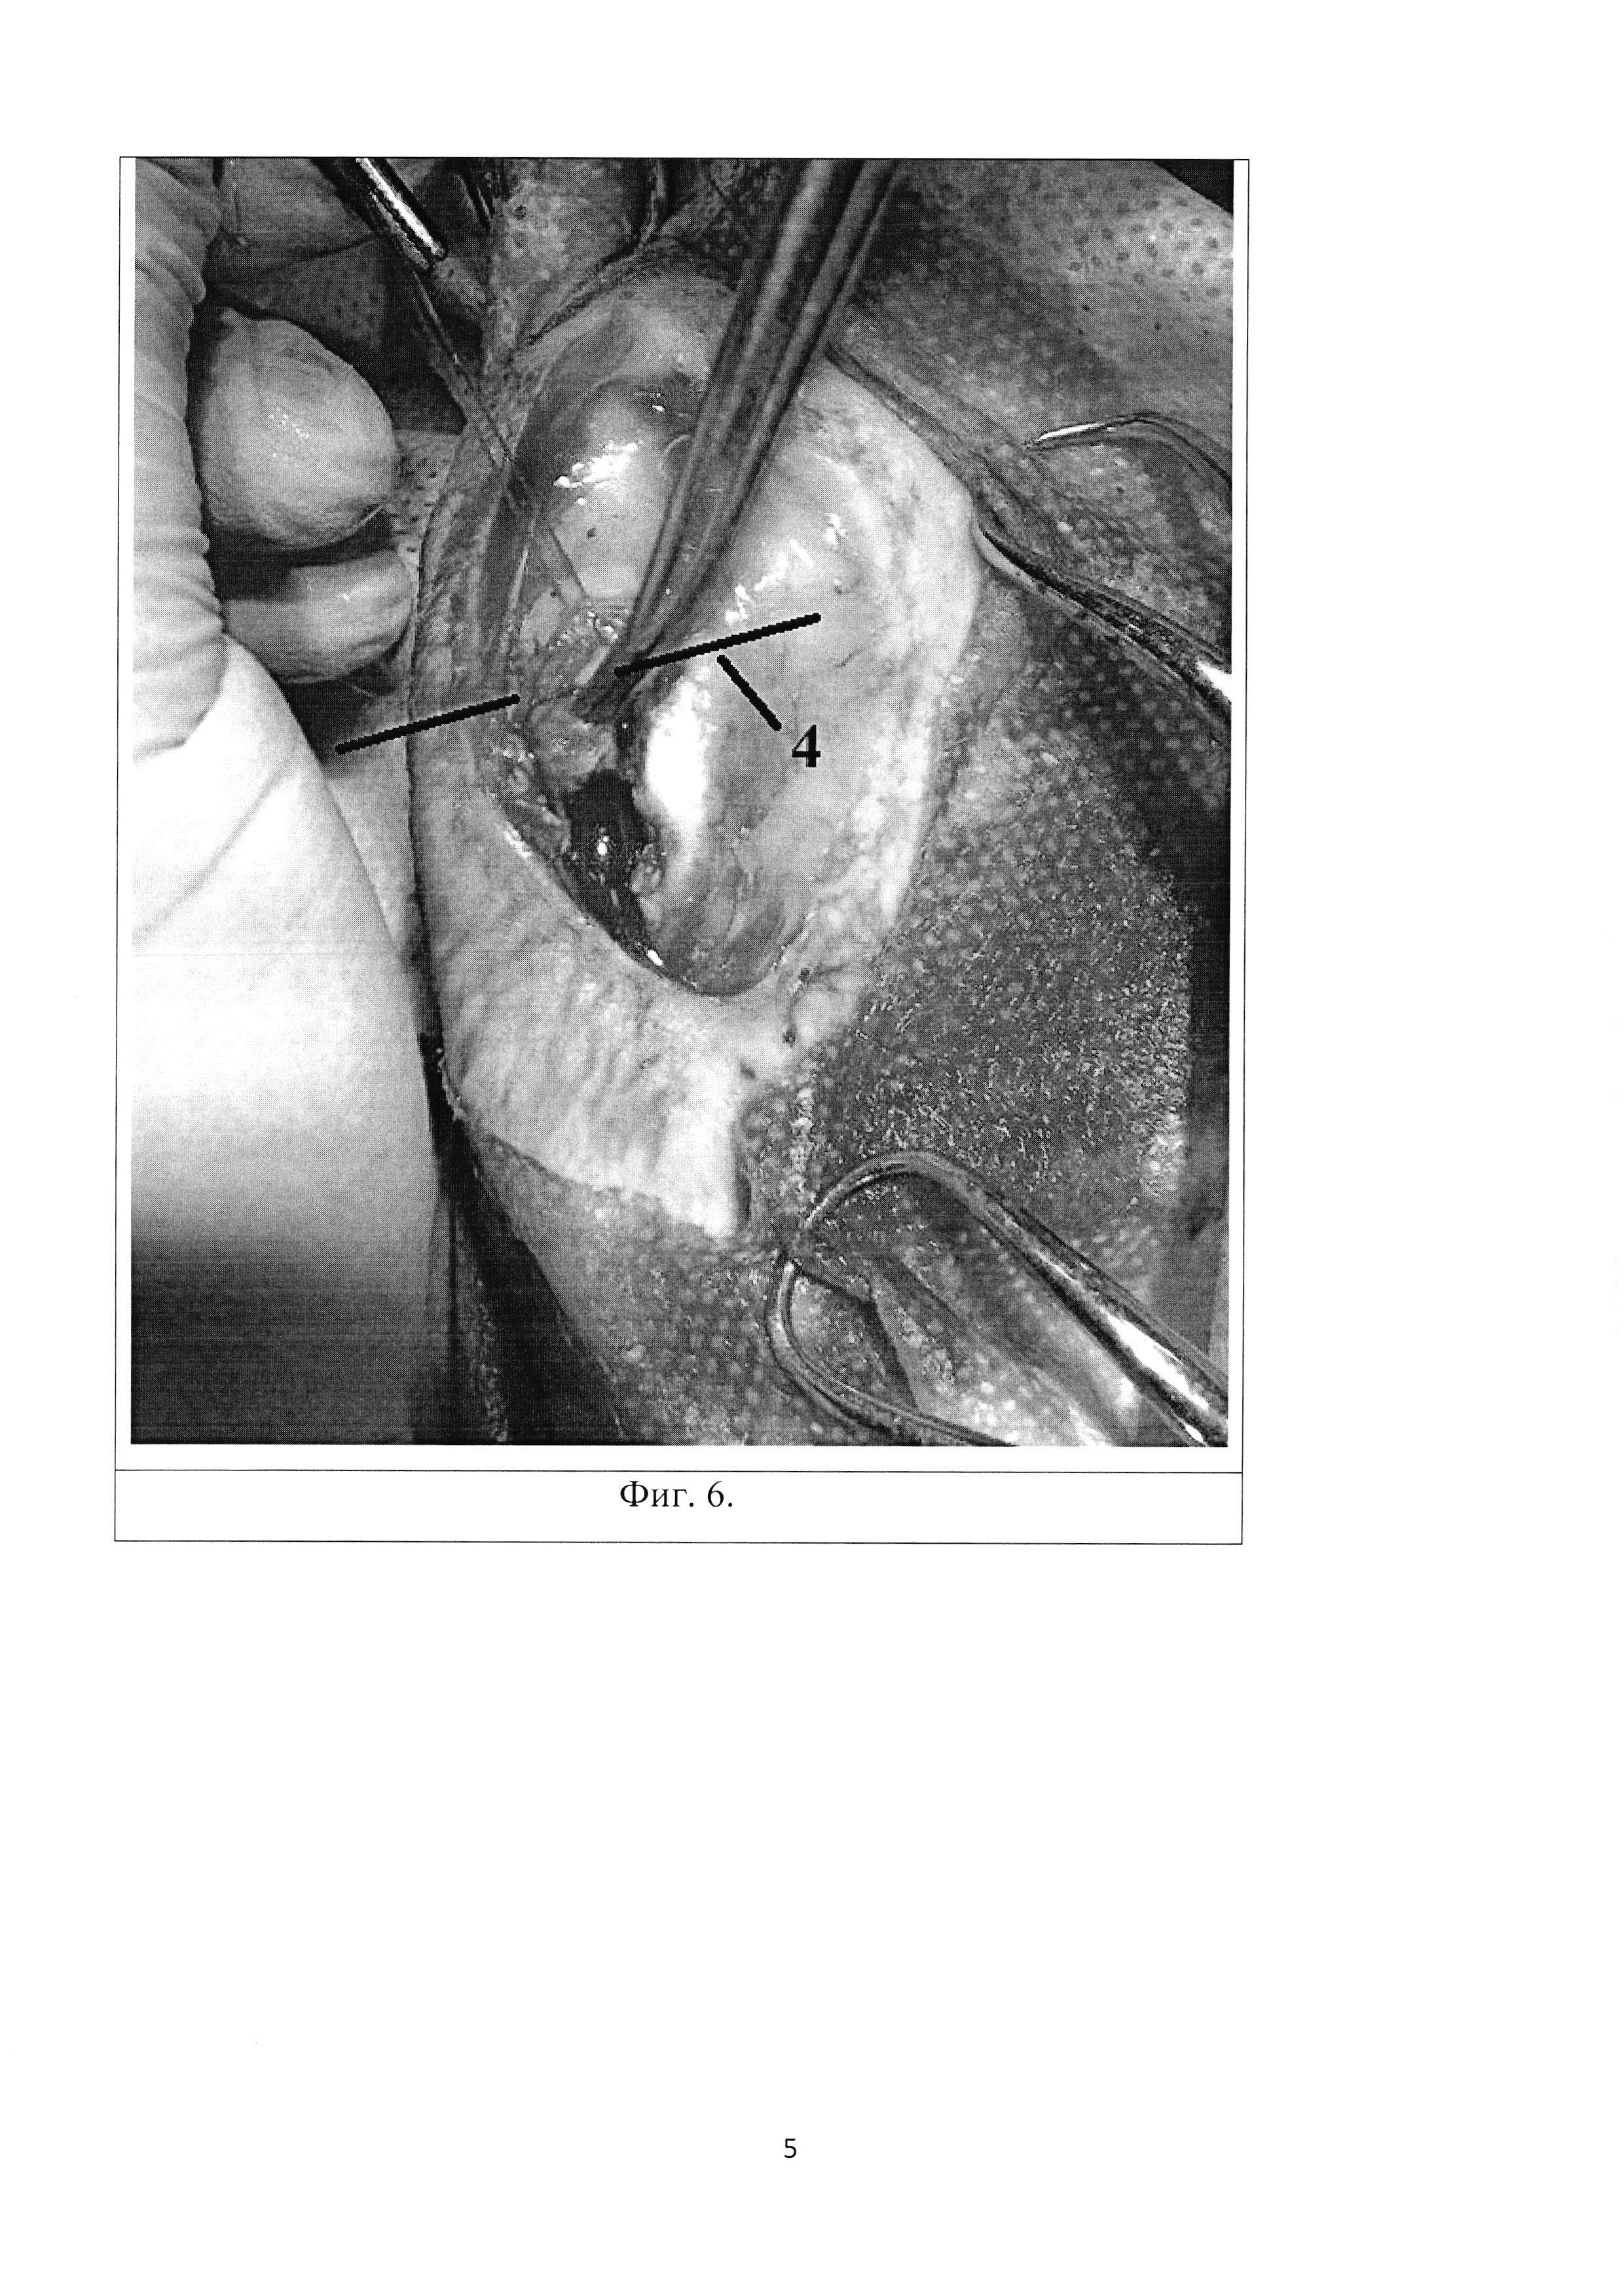

Изобретение относится к экспериментальной медицине, а именно к травматологии и ортопедии, и может быть применимо для изучения пато- и морфогенеза внутрисуставного импрессионного перелома и разработки способов хирургического лечения импресионного перелома эпифиза длинной трубчатой кости. По данным ряда авторов, внутрисуставные переломы в области коленного сустава составляют от 1,5 до 6,9% от всех переломов костей скелета и 10-12,2% от всех внутрисуставных переломов, а переломы мыщелков большеберцовой кости, относящиеся к тяжелым внутрисуставным повреждениям, составляют около 7% от всех переломов опорно- двигательного аппарата. Данный вид повреждений часто сопровождается импрессией костной ткани со стороны суставной поверхности и повреждением важных мягкотканых структур, что следует из особенностей строения сустава (отсутствие значительной мышечной массы, близкое расположение магистральных сосудов, нервов) и сложности его кинематики (Embden D., Stollenwerck G.A., Koster L.A., 2015). Актуальность разработки методов изучения внутрисуставных переломов определяется тем, что для переломов проксимального отдела болыпеберцовой кости характерна высокая частота неблагоприятных функциональных исходов: нередко в отдаленном периоде после травмы развивается деформирующий остеоартроз, контрактуры, нестабильность коленного сустава. Известен способ моделирования субкапитального перелома бедренной кости (Патент G09B 23/28, Способ моделирования субкапитального перелома бедренной кости. Патентообладатель Государственное бюджетное образовательное учреждение высшего профессионального образования Читинская государственная медицинская академия Министерства здравоохранения и социального развития Российской Федерации (RU). Заявка 2490721, Заявл. 2012-02-17, Опубл. 20.08.2013. - 6 с.), при котором обеспечивают равномерное сдавление шейки бедренной кости хирургическим зажимом типа «Москит» до создания субкапитального перелома. Однако данный способ не соответствует картине истинного, так как прикладываемая на кость энергия бранш рабочей поверхности зажима не может точно соответствовать таковой при истинном переломе, по той причине, что истинный перелом предполагает некую осевую перегрузку, возлагаемую на кость. Также данный метод является наиболее травматичным исходя из того, что двустороннее сдавление живой кости может привести к избыточному размозжению костной ткани, а рассечение капсулы тазобедренного сустава может обусловить развитие асептического некроза головки бедренной кости ввиду нарушения ее кровоснабжения. Также следует отметить, что пример субкапитального перелома бедренной кости не соответствует картине импрессионного перелома. Известен способ моделирования несрастающихся переломов длинных трубчатых костей, при котором производят поперечную остеотомию трубчатой кости в ее самом узком месте с помощью пилы Джигли (Патент 2323694, А61В 17/56, Способ моделирования несрастающихся переломов длинных трубчатых костей. Патентообладатель ФГОУ ВПО Белгородская государственная сельскохозяйственная академия. Заявка 2005135524, Заявл. 15.11.2005, Опубл. 10.05.2008. - 6 с.). Однако перелом не соответствует картине истинного ввиду создания его с помощью пилы. Кроме того, данный метод является наиболее травматичным исходя из того, что проволочное витое полотно пилы Джигли обладает слишком большой толщиной (0,5 мм), что может обусловить слишком грубый и избыточный распил кости. Тем самым не отражается этиопатогенез перелома кости. Также следует отметить, что пример субкапитального перелома бедренной кости не соответствует картине импрессионного перелома. Известен способ создания перелома кости в эксперименте, сущность которого состоит в том, что после обезболивания линейным разрезом обнажают поверхность кости на участке предполагаемого перелома (Патент SU 547211, 2 А61В 17/00, Способ создания перелома кости в эксперименте. Патентообладатель Московский городской ордена Трудового Красного Знамени институт скорой помощи им. И.В. Склифосовского. Заявка 1929378/13, Заявл. 28.05.73, Опубл. 25.02.77.). С помощью ножовочного полотна производят надпиливание кортикальной пластинки кости в поперечном направлении в области предполагаемой линии излома. Надпиливание кости производят на глубину кортикального слоя, создавая таким образом зону наименьшей сопротивляемости кости физическим нагрузкам. Захватывают сегмент конечности на протяжении резким ротирующим (при косом расположении линии надпила) или изгибающим (при поперечном надпиле) усилием, производят перелом кости. Однако при данном способе истинный перелом получают только на участке кости на стороне противоположной надпилу, что не соответствует патомеханике травматического перелома. Также данная методика является наиболее травматичной, так как излом кости производиться вручную и сила, прикладываемая к конечности, ничем не контролируема, что может привести к избыточному сгибанию конечности и травме мягких тканей. Нужно сказать, что данный способ моделирования перелома не соответствует картине импрессионного перелома кости. Прототипом данного изобретения стали истинные этиопатогенетические механизмы импрессионного перелома губчатых структур эпифиза любой длинной трубчатой кости. Кортикальная пластинка кости обладает большей, по сравнению с губчатым веществом, площадью цельной поверхности и, следовательно, большей упругостью. Когда на поверхность кортикальной пластинки воздействует определенная однонаправленная сила, запредельная по отношению к трабекулярному веществу, но недостаточная для разрушения компактного, трабекулы губчатого вещества начинают деформироваться и ломаться, а компактное вещество кости начинает заполнять этот объем дефекта, в результате чего образуется импрессионный дефект без четких границ. Технический результат: способ моделирования является высоковоспроизводимым и позволяет приблизить модель к реальному механизму развития патологического процесса. Для создания модели импрессионного внутрисуставного перелома проксимального отдела большеберцовой кости наиболее приближенной к истинной, производится четырехсторонний распил кости (8×7 мм) 1 в области медиального мыщелка большеберцовой кости (Фиг. 1, Фиг. 4) алмазным металлическим отрезным диском (d=10 мм, толщиной = 1,5 мм), отступя 3-5 мм от суставной поверхности дистально. Образовавшийся прямоугольный участок кости извлекается при помощи зажима по типу «москит». Далее производится надлом и смещение части мыщелка 2 (Фиг. 2, Фиг. 5) в дистальном направлении 3 (Фиг. 2, Фиг. 5) в область костного дефекта 1 (Фиг. 2, Фиг. 5), в результате чего образуется импрессионный внутрисуставной перелом медиального мыщелка проксимального отдела большеберцовой кости 4 (Фиг. 3, Фиг. 6, Фиг. 7). Изобретение поясняется иллюстрациями, на которых представлена поэтапная схема проведения внутрисуставного импрессионного перелома. На Фиг. 1. изображен выпиленный прямоугольный участок кости 1 (8×7 мм), который на дальнейших этапах операции будет извлекаться, освобождая под собой вход в костномозговой канал. На Фиг. 2. обозначено направление смещения эпиметафизарного участка с образованием истинного импрессионного дефекта суставной поверхности медиального мыщелка большеберцовой кости, где: 1 - выпиленный прямоугольный участок кости, 2 - часть мыщелка, 3 - направление смещения. На Фиг. 3. изображена готовая модель истинного внутрисуставного импрессионного перелома 4. Фиг. 4. На фотографии виден прямоугольный участок выпиленной кости 1 (8×7 мм), который извлекался, освобождая вход в костномозговой канал. Фиг.5. На фотографии виден смещенный проксимальнее участок медиального мыщелка большеберцовой кости, где: 1 - выпиленный прямоугольный участок кости, 2 - часть мыщелка, 3 - направление смещения. Фиг. 6. На фотографии виден результат операции по моделированию внутрисуставного импрессионного перелома 4, которая окончилась смещением медиального мыщелка большеберцовой кости дистальнее суставной поверхности. Фиг. 7. На фронтальном и сагиттальном КТ-срезе коленного сустава кролика виден результат операции по моделированию внутрисуставного импрессионного перелома 4 медиального мыщелка проксимального отдела большеберцовой кости, имеется область импрессии и дисконгруэнтности суставной поверхности. Способ осуществляют следующим образом. Животное погружают в наркоз и обрабатывают область оперативного вмешательства, выполняют доступ к медиальному мыщелку большеберцовой кости путем острой диссекции мягких тканей с внутренней стороны голени. Мягкие ткани разводятся, в результате чего обеспечивается доступ к участку кости с надкостницей; костным распатором Фарабефа надкостница сдвигается в дистальном направлении. Анатомическим ориентиром для дальнейших действий является общее сухожильное крепление мышц внутренней поверхности бедра - «поверхностная гусиная лапка». Алмазным металлическим отрезным диском (d=10 мм, толщиной = 1,5 мм) производится четырехсторонний распил кости (7×8 мм) 1 в области медиального мыщелка большеберцовой кости (Фиг. 1, Фиг. 4) перед вышеуказанным анатомическим образованием, на глубину кортикальной пластинки кости, без проникновения в полость коленного сустава. Извлекается прямоугольный участок кости. Производится смещение мыщелка 2 (Фиг. 2, Фиг. 5) в дистальном направлении 3 (Фиг. 2, Фиг. 5) в область образовавшегося костного дефекта (Фиг. 2, Фиг. 5) для обеспечения дисконгруэнтности суставной поверхности (Фиг. 3). Рана послойно ушивается. Способ моделирования внутрисуставного импрессионного перелома большеберцовой кости иллюстрируется следующим примером. Пример Для выполнения модели был взят кролик породы «Шиншилла» массой 2600 грамм. При работе с животным соблюдались «Международные рекомендации (этический кодекс) по проведению медико-биологических исследований с использованием животных» (1985). После погружения животного в парентеральный наркоз и традиционной обработки операционного поля был выполнен разрез кожных покровов, тупым и острым способом был осуществлен доступ к медиальному мыщелку большеберцовой кости. После разведения мягких тканей, костным распатором Фарабефа надкостница сдвигалась дистально. Далее алмазным металлическим отрезным диском производился четырехсторонний распил кости перед сухожильным расширением «Гусиная лапка». Участок выпиленной кости извлекался и производилось смещение мыщелка в дистальном направлении в область образовавшегося костного дефекта для обеспечения дисконгруэнтности суставной поверхности. Рана послойно ушивалась. Таким образом, предлагаемый способ моделирования является высоко воспроизводимым и позволяет приблизить модель к реальному механизму развития патологического процесса. В ходе эксперимента была сделана серия снимков на КТ аппарате Toshiba Aquilion 64, пример данного снимка представлен на Фиг. 7.